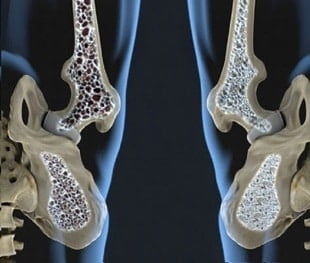

La osteoporosis es una enfermedad esquelética caracterizada por una resistencia ósea disminuida que predispone al aumento del riesgo de fractura. Afecta fundamentalmente a las mujeres después de la menopausia, aunque también puede presentarse antes o hacerlo en hombres y, en menor medida, en niños.

“Más de 10 millones de personas en EEUU padecen osteoporosis, una afección que es más común en mujeres que han superado la menopausia. Las personas con osteoporosis tienen huesos debilitados que son más propensos a fracturarse”, dice la nota de la FDA.